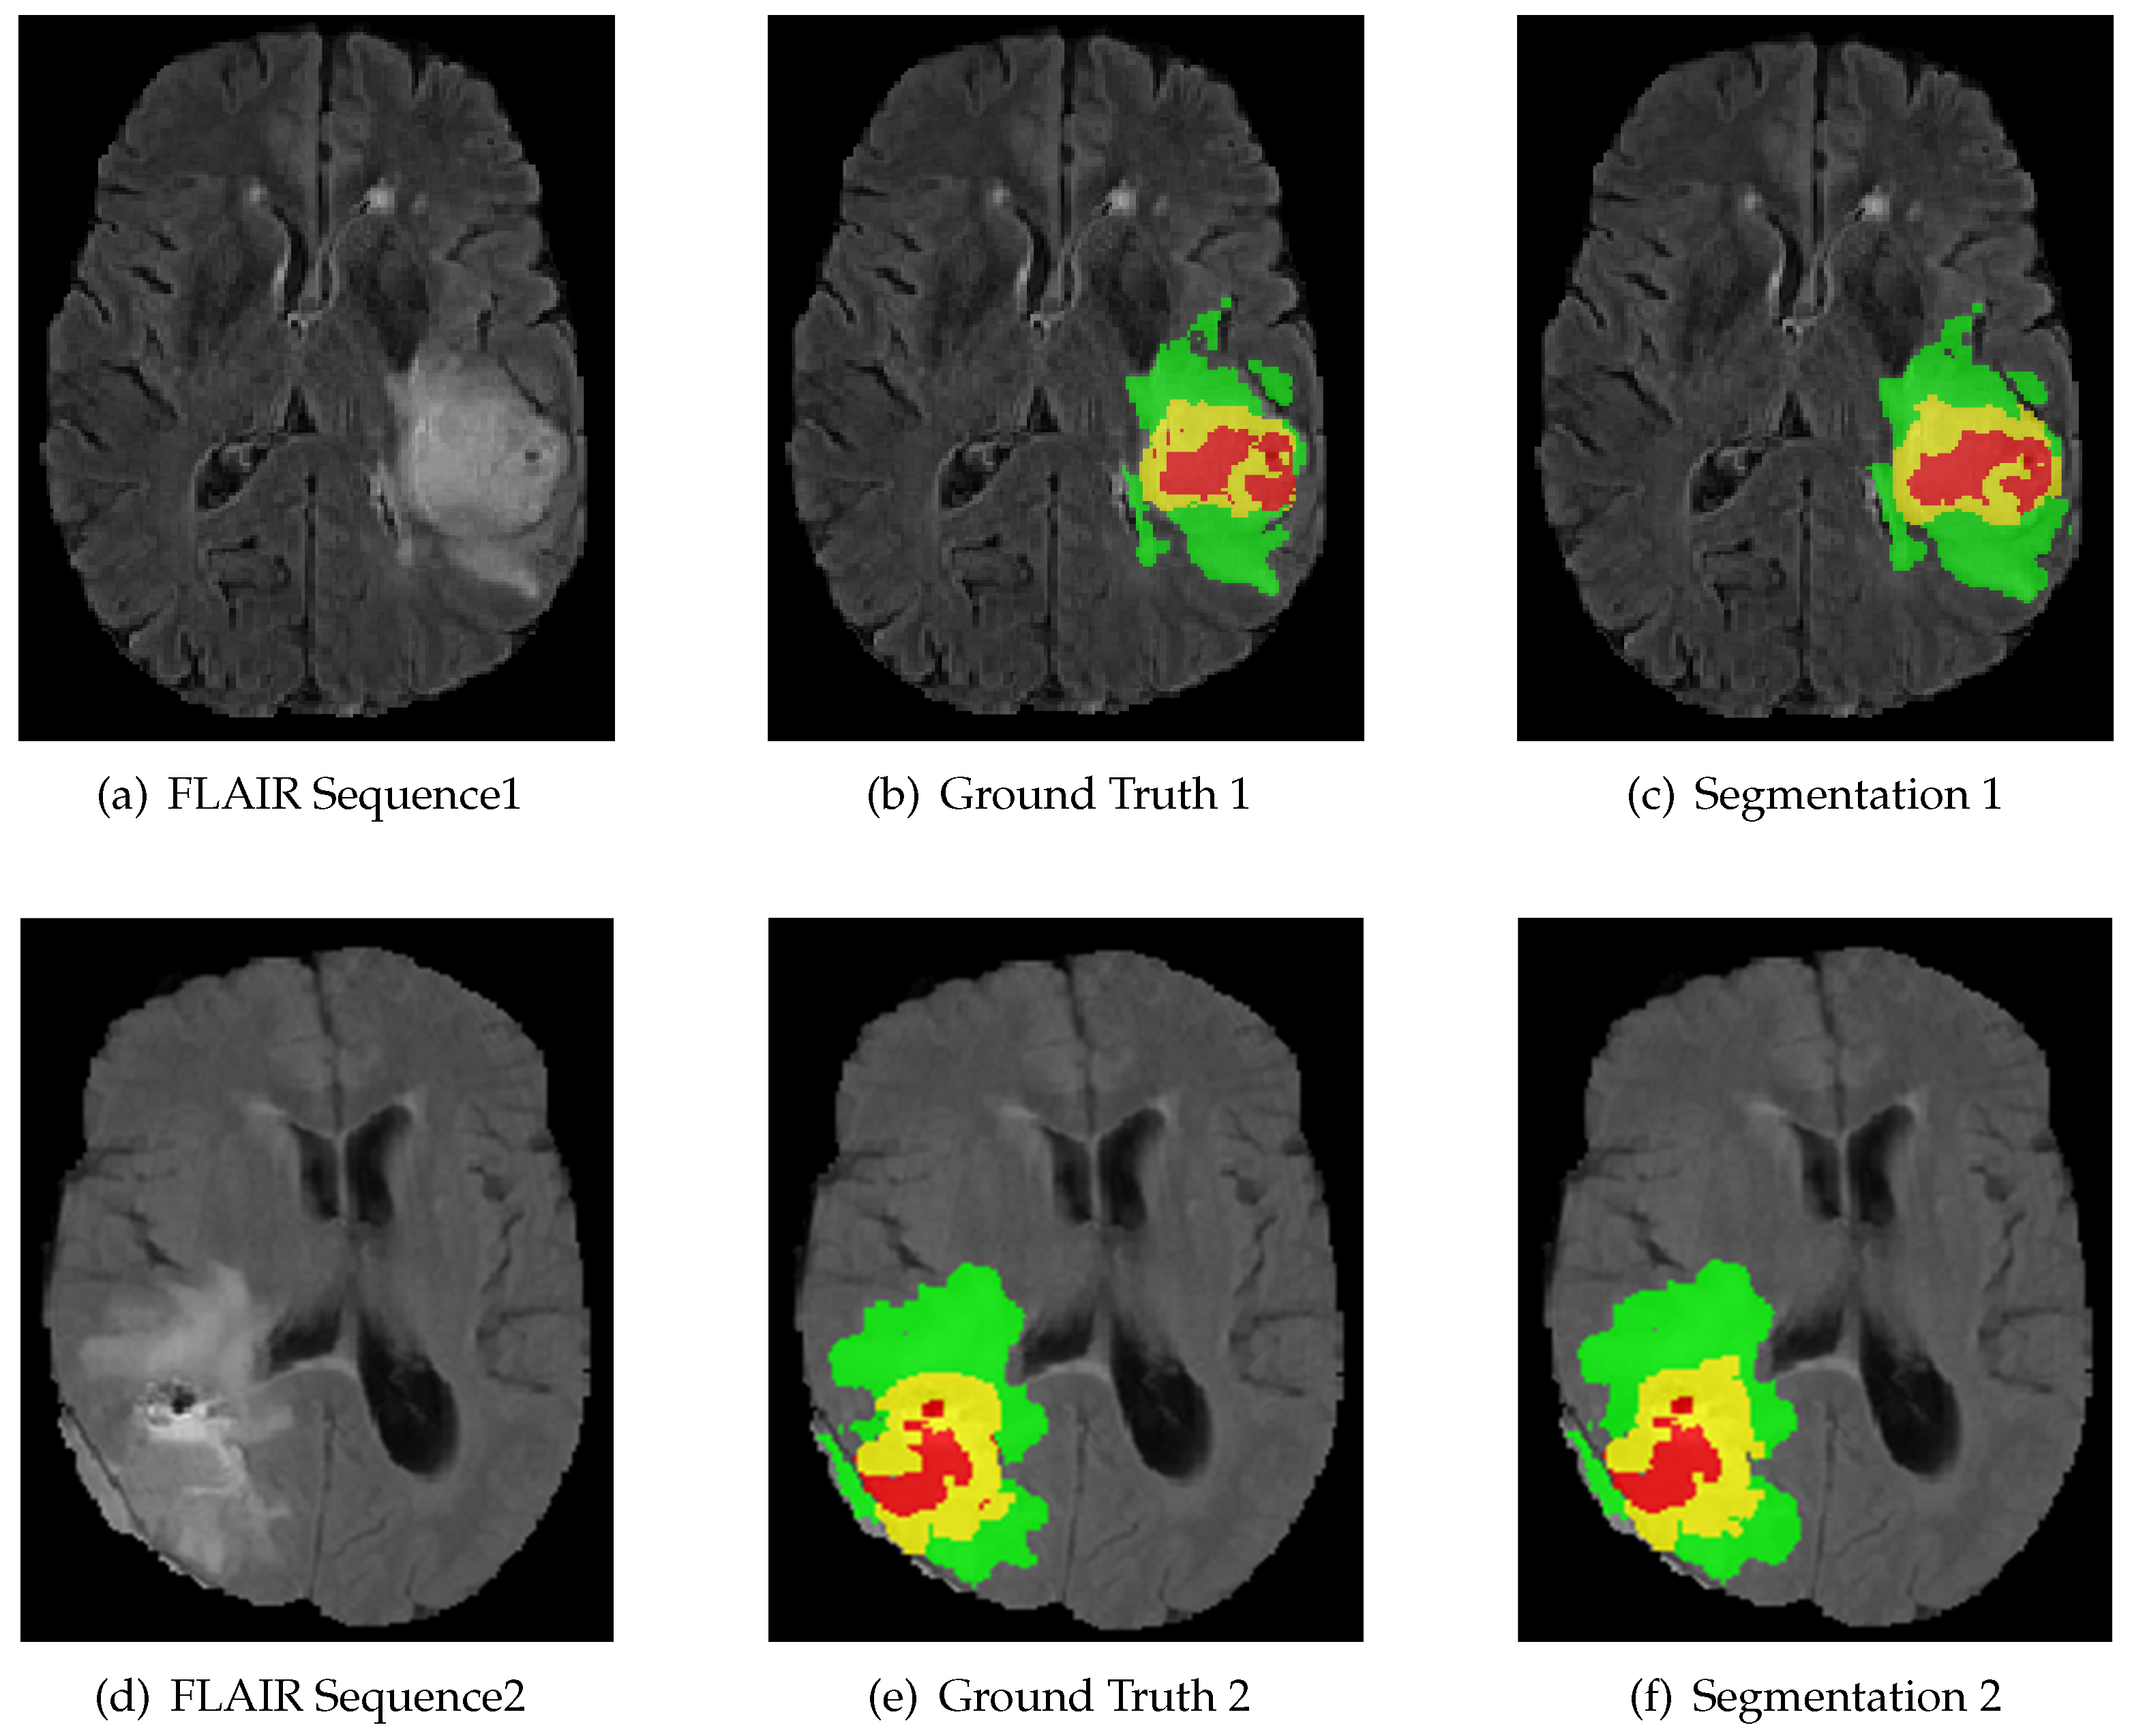

The proposed RMFNet achieves the best results on the brain tumor segmentation from multi-modal 3D MRIs. Table 1 shows the results of our model and comparison model, our results are shown in bold on the last line. The following evaluation results can be used for analysis. In fact, the proposed algorithm achieves a Dice value of 89.62% for whole tumor, 83.65% for tumor core and 78.72% for enhancing tumor. The HD value achieves 5.96 for whole tumor, 7.56 for tumor core and 3.94 for enhancing tumor. According to Dice score, it is observed that, compared with previous models, our model remarkably outperforms 3D U-Net [32] on the BraTS 2018 validation dataset. Compared with the best algorithm [38], we can see that our method only has marginal performance gaps of 5.12% for the enhancing tumor. However, our RMFNet only has 2.65 M parameters and 37.24 G FLOPs, and our model has 10 times less FLOPs than [38]. It is observed that our method can accurately segment different tumor subregions without requiring many parameters, and can outperform the other methods on the BraTS 2018 validation dataset. Thus, our RMFNet is a more efficient algorithm and has the potential of our method in multi-modal 3D MRI image segmentation tasks. The part segmentation results are shown in Figure 5.

Figure 5.

The result of using RMFNet with corresponding fluid attenuated inversion recovery (FLAIR) slice and ground truth on BraTS 2018 Training dataset. Red: necrotic and non-enhancing tumor (label 1); green: peritumoral edema (label 2); yellow: active/enhancing tumor (label 4).